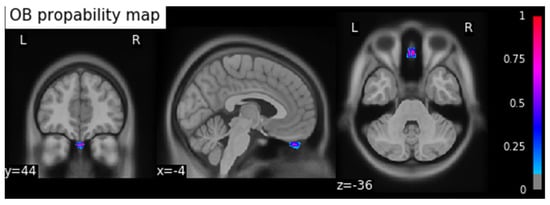

This process resulted in a probability map for the OBs in MNI space. To calculate the coordinates of the center of gravity (COG) of the OB, we applied a threshold of 0.5 to the resulting OB probability map and calculated the coordinates in MNI space (xyz: −4/44/−36) using the SciPy python library [], and saved the result as a binary image (Figure 1).

OB probability map: background image MNI ICBM 2009c Nonlinear Asymmetric template, threshold 0.5. The coordinates of the COG are xyz: −4/44/−36. (x: sagittal, y: frontal, z: axial orientations). The colormap indicates the probability from 0 to 1.